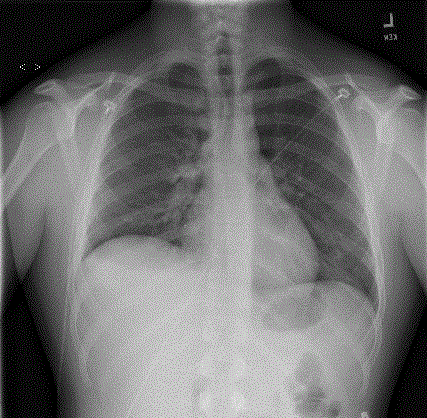

In the ER his vital signs were significant for fever to 40.1 C, tachycardia, tachypnea, and hypoxia requiring 3L oxygen. Physical exam revealed significant diaphoresis and decreased breath sounds at the right base. He had dullness to percussion over the right lower lung field, but no egophany was noted. A chest X-Ray showed possible right pleural effusion with no consolidation (Figure 1). CTA was obtained and showed no pulmonary emboli but found right air space concerning for pneumonia and an abscess superior to his right lower lobe bronchus. Blood cultures were obtained, he was given fluids and started on Ceftriaxone and Azithromycin (Figure 2).

Figure 1. Chest X-Ray